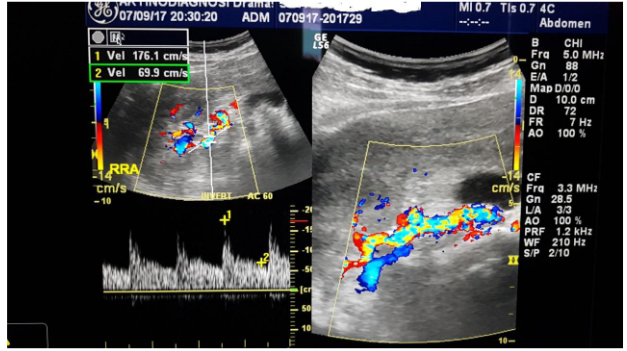

Urine test did not show albuminuria, while renal function deteriorated in the last six months: urea was increased from 25 to 49mg/dl and creatinine from 0.7mg/dl to 1.3mg /dl. In kidney ultrasound the right kidney was at 11cm while the left kidney was smaller, at 9.5cm. The triplex of the renal arteries showed a significant degree of stenosis in the left renal artery (Figures 1 & 2). The maximum velocity in doppler must not exceed 1.4 m/s while our patient has 5m/s in the left artery! Additional pathological findings are: (Figure 3)

Figure  2 Doppler of right renal artery.

Resistance index 0.49 (RI:0.6-0.7), is a general indicator of renal parenchymal disease. In patients with severe renal artery stenosis >75-80%, in the early stages of the disease the resistance index is low (RI<0.6). Is attributed to marked vasodilation promoted by self-regulating endothelial mechanisms and aimed at protecting the ischemic kidney. As the disease develops and affects the renal parenchyma, the vascular resistance increases and consequently increase RI>0.8. The resistance index has not only diagnostic but also predictive value: RI>0.8 indicates severe parenchymal disease and is an unfavorable indicator of renal function repair and correction of arterial hypertension after reperfusion.

The acceleration time 0,12s (AT:<0,07sec), indicative renal low flow. The patient was then subjected to magnetic angiography of renal arteries (MRA) confirming the triplex’s findings: 90% stenosis of left renal artery immediately after the outgrowth of the abdominal aorta (Figure 4). In the radioactive nephrogram, impaired left kidney function is demonstrated at 36% in the relative involvement of total renal function (split function), as opposed to the right kidney that contributes to 64% of glomerular function (Figure 5). In the same test was calculated with gates technique the GFR in the right kidney at 76.2ml/min/1,73m2,while in the left kidney 26.6ml/min/1,73m2.